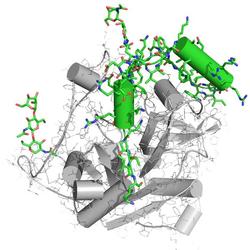

Molekulare Struktur des Enzyms Cathepsin B aus dem Erreger der Schlafkrankheit, dem Parasiten Trypanosoma brucei. Die blockierenden Peptid- und Kohlenhydratketten sind grün dargestellt. Sie stellen die erste neue biologische Strukturinformation dar, die mit einem Freie-Elektronen-Laser gewonnen wurde. Bild: Karol Nass, CFEL |

Darüber hinaus hat die In-vivo-Kristallisation in Insektenzellen einen weiteren, entscheidenden Vorteil: Auf diese Weise wurde das Cathepsin B in seiner natürlichen Konfiguration "eingefroren". Das Enzym arbeitet als eine Art molekulare Schere, die andere Proteine zerteilt. Es wird daher im Organismus in einer inaktivierten Form hergestellt, bei der ein kleines Eiweißmolekül, ein sogenanntes Peptid, die Schere blockiert. Erst wenn die Schere gebraucht wird, aktiviert die Zelle das Enzym und löst das Peptid.

"Dank des angekoppelten Peptids konnten wir unter einen bislang unzugänglichen Strukturbereich des Cathepsins schauen", erläutert Betzel. Dort enthüllte die Analyse deutliche Unterschiede der Peptid-Bindungsstellen am Cathepsin B zwischen Parasit und Mensch, die sich für einen maßgeschneiderten künstlichen Hemmstoff nutzen lassen, der gezielt das Parasiten-Enzym blockiert. "Auf diese Weise hat uns die Natur einen grundlegenden Bauplan dafür geliefert, wie ein künstlicher Hemmstoff für das Enzym des Parasiten aussehen könnte." Der nächste Schritt wäre die Herstellung und der Test eines solchen Hemmstoffs im Labor.